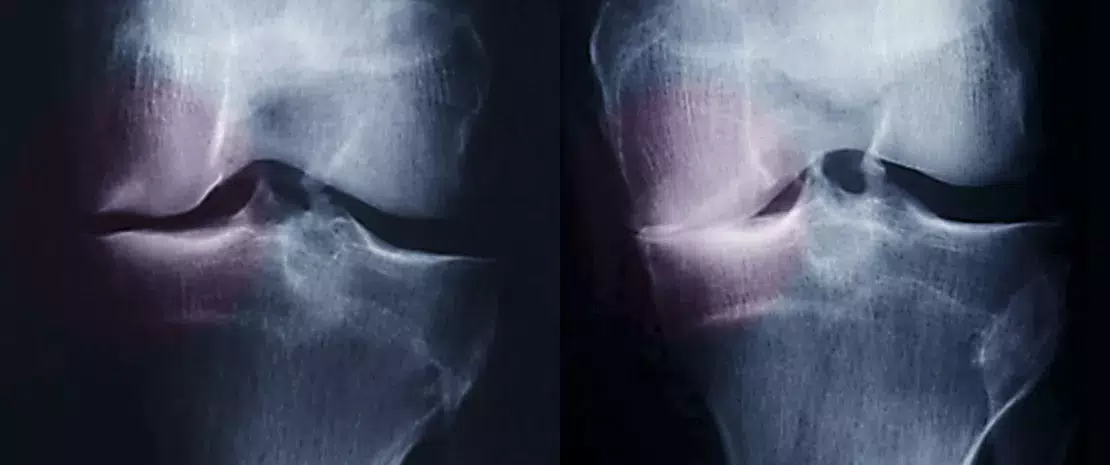

Z powodu nadmiernego obciążenia stawów osoby z nadwagą są bardziej narażone na artrozę. Jak jednak zidentyfikować osoby najbardziej zagrożone? Być może dzięki ich mikrobiocie jelitowej związanej z wieloma chorobami zapalnymi, między innymi z artrozą.

W Chinach na populacji z nadwagą (25<BMI1<30) przeprowadzono badanie prospektywne, w ramach którego 182 próbki stolca pobrane od 86 pacjentów dotkniętych nadwagą i artrozą (25 mężczyzn i 61 kobiet w wieku od 50 do 72 lat) i 96 osób z nadwagą bez artrozy (40 mężczyzn i 56 kobiet w wieku od 50 do 76 lat) zostały zsekwencjonowane (RNA rybosomalne 165) w celu scharakteryzowania składu ich mikrobioty. Wyniki? Zróżnicowanie i bogactwo mikrobioty jelitowej tych pacjentów z nadwagą były mniejsze w przypadku artrozy, co – zdaniem autorów – może dowodzić dysbiozy związanej z chorobą. W przypadku artrozy liczebność dziewięciu typów była znacznie zmieniona (podwyższona lub obniżona, zależnie od typu). Dotyczy to między innymi typów Firmicutes i Bacteroidetes, których stosunek używany jako wskaźnik dysbiozy jest znacznie wyższy u pacjentów dotkniętych artrozą. Ponadto pacjenci z nadwagą cierpiący na tę choroba różnili się od nie dotkniętych nią liczebnością 87 rodzajów bakterii. Wszystkie one pozwoliły badaczom przetestować interesujące ich biomarkery choroby.

Przewidywanie zagrożenia artrozą za pomocą 7 biomarkerów

Na podstawie wcześniejszych wyników badacze zidentyfikowali siedem pochodzących z mikrobioty jelit biomarkerów, które mogą umożliwić opracowanie nieinwazyjnego narzędzia do wczesnej oceny zagrożenia osób z nadwagą artrozą: trzy rodzaje bakterii nadmiernie liczne u pacjentów chorych na artrozę (Gemmiger, Klebsiella i Akkermansia) i cztery zbyt mało liczne u tych samych pacjentów (Bacteroides, Prevotella, Alistipes i Parabacteroides). Łącznie biomarkery te pozwalają precyzyjnie przewidzieć zagrożenie artrozą (powierzchnia pod krzywą wynosi 83,36%). Wśród nich decydującą rolę gra rodzaj Bacteroides. Autorzy uważają go nawet za możliwy cel leczenia artrozy.